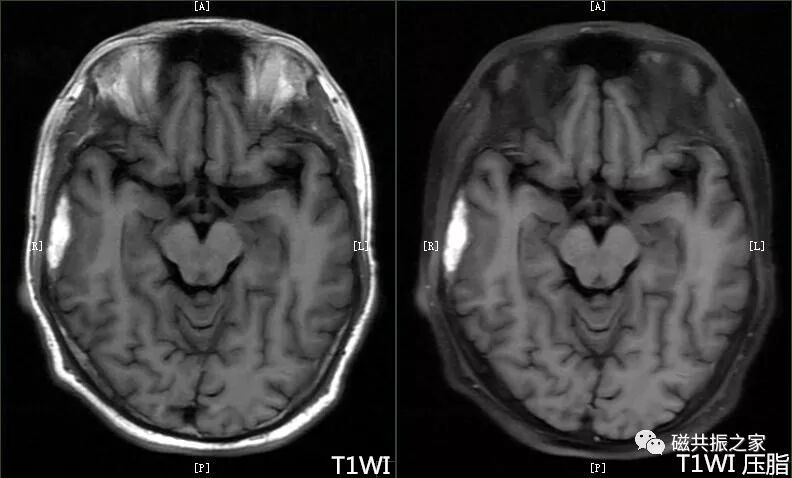

加扫抑脂t1wi 序列以明确是否为脂肪病类变,见上图t1wi flair序列